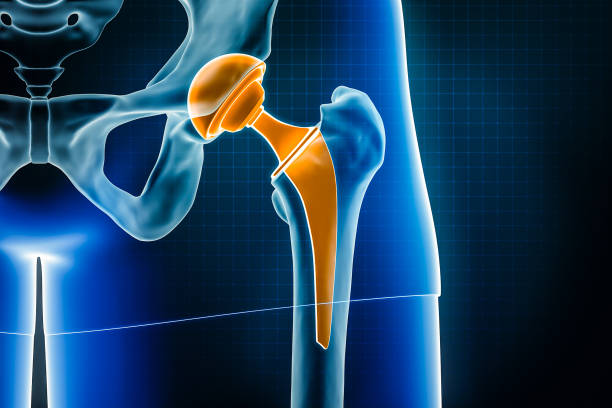

Advanced Joint Replacement Surgery in Noida

When it comes to joint replacement surgery, ShardaCare – Healthcity is your trusted partner. We offer expert Knee Replacement Surgery, Hip Replacement Surgery, and Ankle Replacement Surgery in Noida to help you regain your mobility and reduce pain. Our highly skilled surgeons use advanced techniques to perform joint replacements, minimising downtime and accelerating recovery.